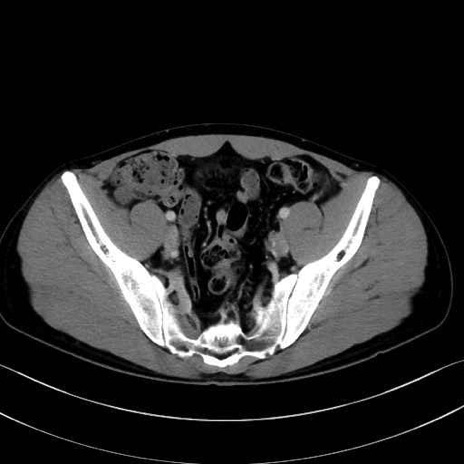

2. 腸腰筋群と骨盤底筋

大腰筋 (Psoas major)

腸骨筋 (Iliacus)

肛門挙筋 (Levator ani)